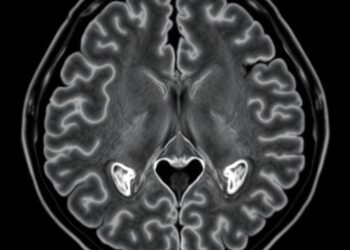

In a groundbreaking advancement poised to transform forensic and pathological investigations, researchers have unveiled their initial experiences utilizing a 0.31 ...